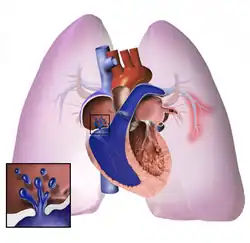

.jpg)

The pathogenesis of pulmonary arterial hypertension (WHO Group I) involves the narrowing of blood vessels connected to and within the lungs. This makes it harder for the heart to pump blood through the lungs, as it is much harder to make water flow through a narrow pipe as opposed to a wide one. Over time, the affected blood vessels become stiffer and thicker, in a process known as fibrosis. The mechanisms involved in this narrowing process include vasoconstriction, thrombosis, and vascular remodeling (excessive cellular proliferation, fibrosis, and reduced apoptosis/programmed cell death in the vessel walls, caused by inflammation, disordered metabolism and dysregulation of certain growth factors).[27][28] This further increases the blood pressure within the lungs and impairs their blood flow. In common with other types of pulmonary hypertension, these changes result in an increased workload for the right side of the heart.[16][29] The right ventricle is normally part of a low pressure system, with systolic ventricular pressures that are lower than those that the left ventricle normally encounters. As such, the right ventricle cannot cope as well with higher pressures, and although right ventricular adaptations (hypertrophy and increased contractility of the heart muscle) initially help to preserve stroke volume, ultimately these compensatory mechanisms are insufficient; the right ventricular muscle cannot get enough oxygen to meet its needs and right heart failure follows.[16][28][29] As the blood flowing through the lungs decreases, the left side of the heart receives less blood. This blood may also carry less oxygen than normal. Therefore, it becomes harder and harder for the left side of the heart to supply sufficient oxygen to the rest of the body, especially during physical activity.[30][31][11] During the end-systolic volume phase of the cardiac cycle, the Gaussian curvature and the mean curvature of the right ventricular endocardial wall of PH patients were found to be significantly different as compared to controls.[32]

In PVOD (WHO Group I), pulmonary blood vessel narrowing occurs preferentially (though not exclusively) in post-capillary venous blood vessels.[33] PVOD shares several characteristics with PAH, but there are also some important differences, for example differences in prognosis and response to medical therapy.[34]